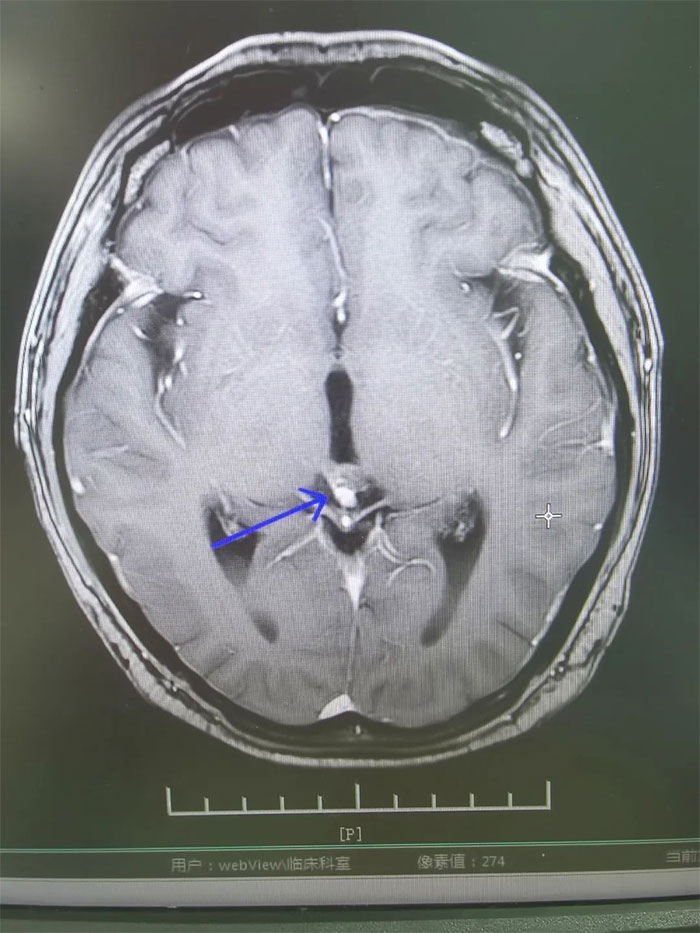

▲ 放疗前病灶影像定位

肿瘤科(放疗)王晓东主任详细了解了患者的病史,并进一步完善检查。在查体时,小刚表示近期感到头痛,偶有恶心呕吐。垂体增强MRI示:垂体术后,垂体区及松果体区占位,视交叉受压,右侧海绵窦局部受累,第三脑室扩大,梗阻性脑积水形成,提示病情进一步加重。

▲ 放疗后复查,病灶明显缩小

经过一个完整疗程的放疗,患者没有出现明显并发症,头痛、恶心呕吐症状得到缓解。复查MRI,影像显示病灶明显缩小,梗阻性脑积水消失。进一步完善检查评估后,小刚已顺利出院。眼见短时间内病情即得到控制,小刚对生活又重拾信心,表示一定会以积极的心态面对人生。